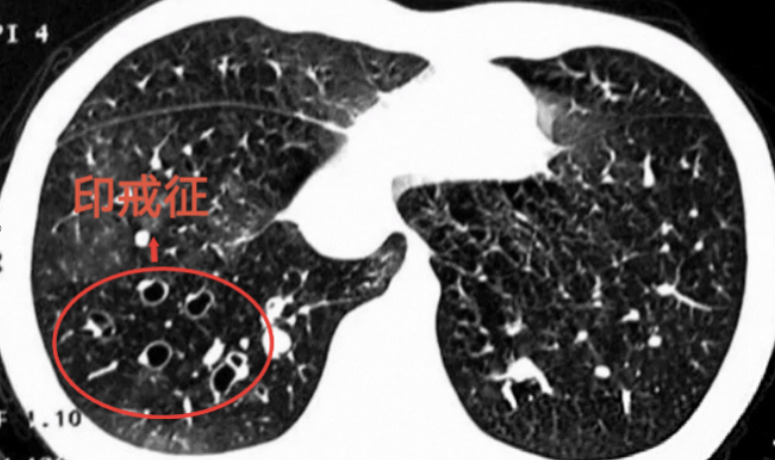

“这是支气管扩张症(简称:“支扩”)的典型CT图像表现之一,医学上称之为‘印戒征’。”该科副主任医师何梦璋介绍说,当支气管反复感染、受损后,可出现变形扩大,管壁增厚,圆圈就是扩大了的支气管,就像戒指的指环,小白点是正常肺动脉的横截面,像钻石。扩张的支气管跟正常的血管在一起,看上去就像镶着钻石的“戒指”。

但连续熬夜加班几天后,林女士不仅咳嗽咳痰加剧,竟咯出了一口鲜红色的血痰,她赶紧到广州医科大学附属第二医院(简称:广医二院)番禺院区呼吸内科就诊。医生建议她拍胸部CT检查,结果发现CT片上,几枚“钻戒”形状的病灶清晰可见。她怎么也没想到会以这种方式与“钻戒”相遇!